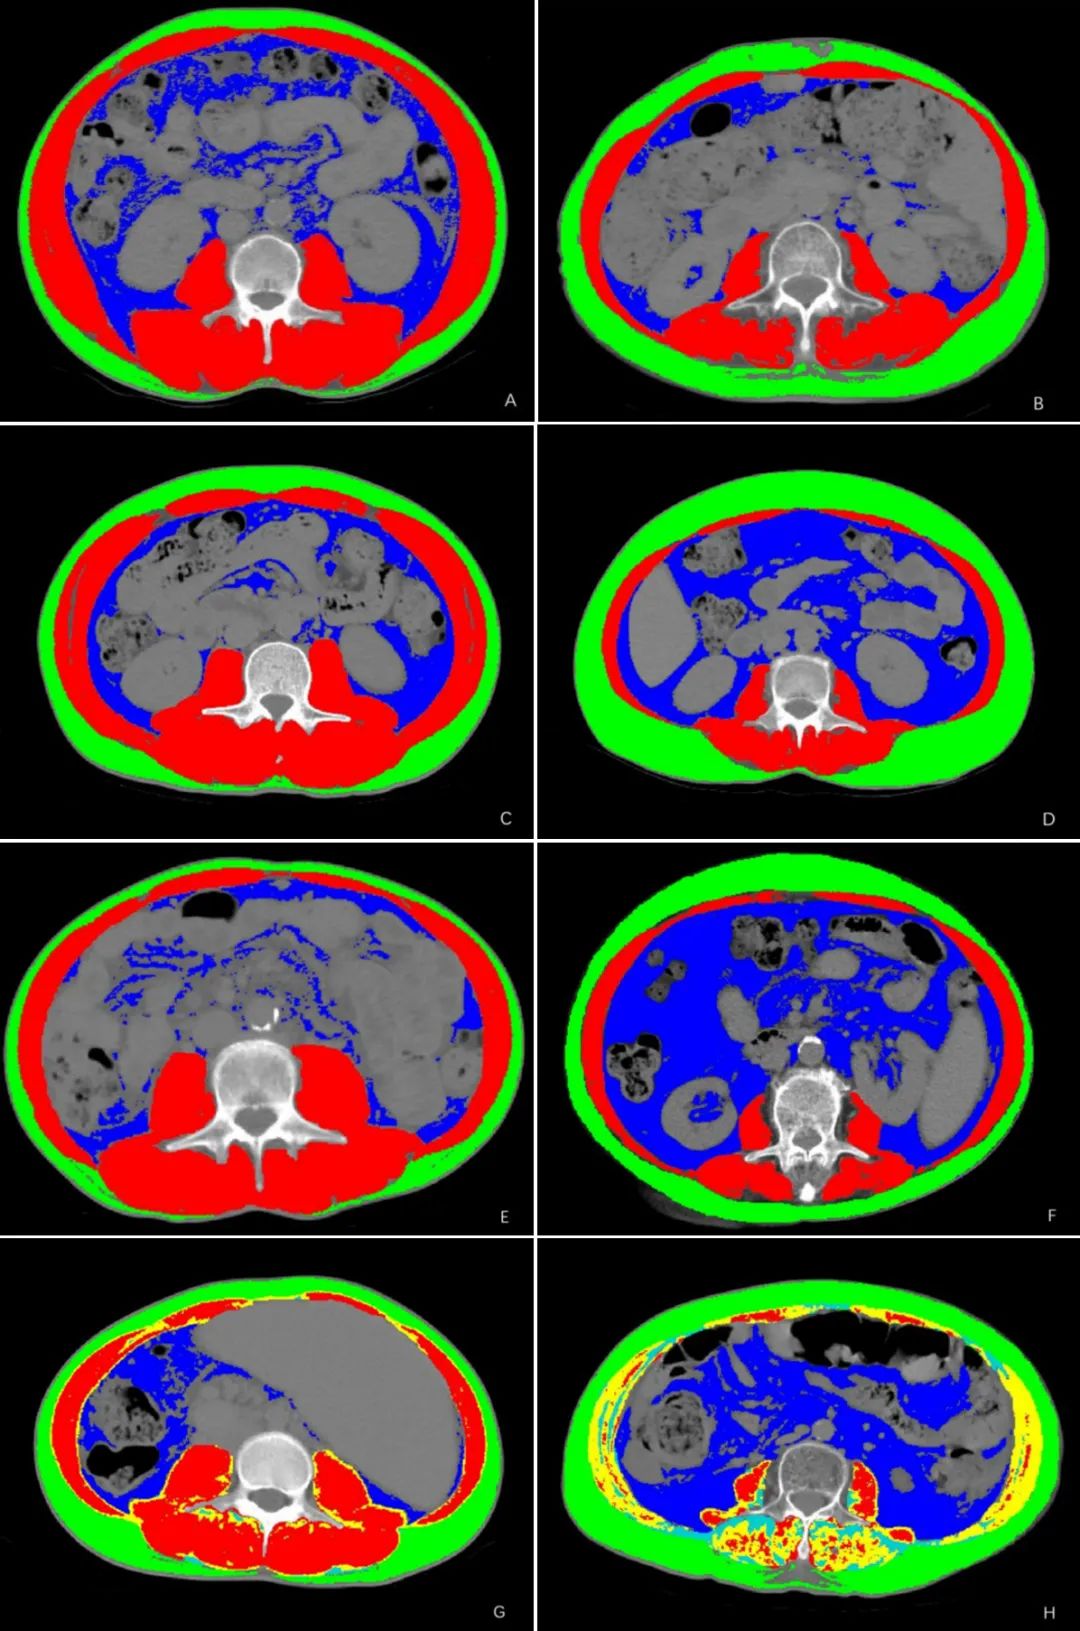

该研究最终纳入了158例被诊断为肝硬化的患者,年龄(57.1±12.6)岁。其中,60例患者(37.97%)为超重,96例患者(60.76%)为男性,54例患者被诊断为酒精性肝硬化。对L3- CT图像的分析显示,85例患者表现出肌少症(图1A和1B),22例患者表现肌少症性肥胖(图1C和1D),66例患者表现出内脏肥胖(图1E和1F),68例患者表现出肌肉脂肪变性(图1G和1H)。统计分析显示,年龄、L3骨骼肌密度(SMD)和L3内脏脂肪面积(VATA)与这三种异常身体成分状态显著相关(P<0.05)。肌少症性肥胖和肌肉脂肪变性患者的内脏肥胖患病率显著高于肌少症患者(所有P<0.05)。此外,肌少症患者与较低的BMI、女性和腹水显著相关,而肌肉脂肪变性患者与较高的BMI和男性显著相关(P<0.05)。此外,与无肌少症性肥胖的患者相比,肌少症性肥胖个体中有高血压病史的患病率存在显著差异(P=0.020)。

图1. 肝硬化患者身体成分的CT图像

比较两位患者,一位没有肌少症(A),一位有肌少症(B)(SMI:70.48 cm2/m2 vs. 21.97 cm2/m2);一位没有肌少症性肥胖(C),一位有肌少症性肥胖(D)(VATA:58.35 cm2 vs. 125.8 cm2;SMI:55.22 cm2/m2 vs. 31.41 cm2/m2)。一位没有内脏肥胖(E),一位有内脏肥胖(F)(VATA:34.2 cm2 vs. 198.5 cm2;VSR:0.90 vs. 1.67)。比较两位患者,一位没有肌肉脂肪变性(G),一位有肌肉脂肪变性(H)(SMD:45.3 HU vs. 14.5 HU)。高密度(33~150 HU)的骨骼肌区域以红色突出显示,低密度肌肉(-29~32 HU)以黄色突出显示。肌内脂肪区域(-190~-30 HU)以浅蓝色突出显示。皮下脂肪区域以绿色突出显示。内脏脂肪区域以深蓝色突出显示。